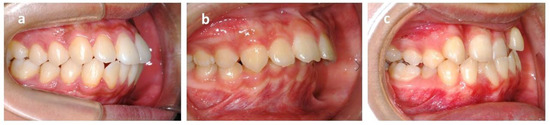

2.5. The Indices of Complexity Outcome and Need (ICON)

ICON is an index of complexity outcome and need that is used for assessing the orthodontic treatment need (Figure 4). ICON has been proposed as a multipurpose occlusal index, including dental components such as crowding measured with the irregularity index/spacing (sagittal dimension), cross bites (transverse dimension), anterior open bite/overbite (vertical dimension), and sagittal posterior occlusion relationship as well as the esthetic component. The esthetic component comprised 10 color photographs showing dentition in the frontal view graded from 1 (most attractive) to 10 (least attractive). The dental indices were documented as numeric values according to the standard. The final ICON score was divided into malocclusion complexity grades (<29 = easy, 29–50 = mild; 51–63 = moderate, 64–77 = difficult, >77 = very difficult). A cutoff point of 43 was set to mark a definite need for orthodontic treatment [41].

Figure 4. Dental component scale of index of complexity outcome and need (ICON). (a) Crowding: crowding occurs when there is a discrepancy between the space required by teeth and the space available in the jawbone. The irregularity index is used for measurement. (b) Spacing: the opposite of crowding, the space available is larger than space required. (c) Posterior buccal crossbite: buccal cusp of the mandibular dentition occludes lingually to the lingual cusp of the maxillary dentition. (d) Posterior lingual crossbite: buccal cusp of the mandibular dentition occludes buccally to the buccal cusp of the maxillary dentition. (e) Anterior crossbite: maxillary incisors occlude lingually to mandibular incisors. (f) Open bite: there is no vertical overlap between the maxillary and mandibular incisors. (g) Overbite: the vertical overlap of the incisors.